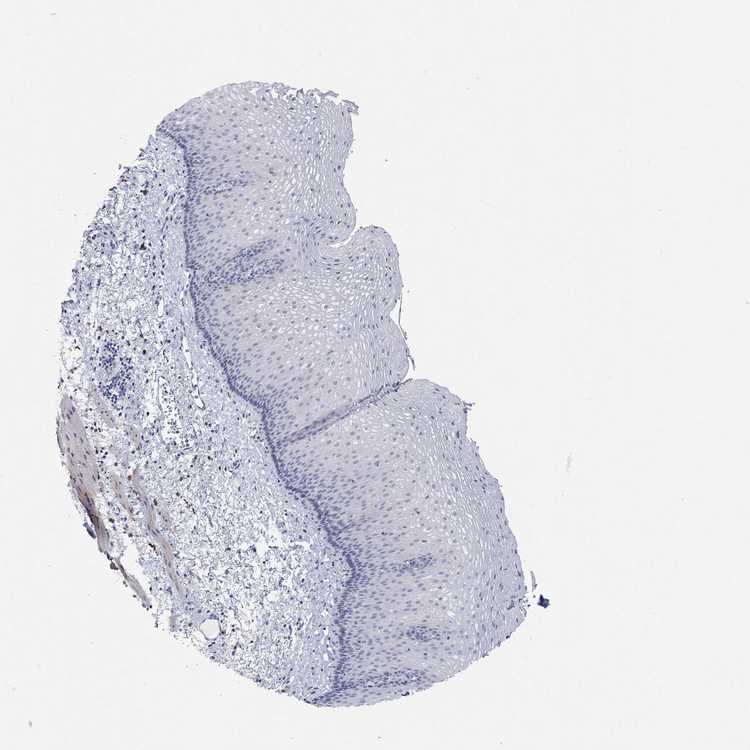

ESOPHAGUS - Antibody stainingi

Antibody staining in the annotated cell types in the current human tissue is reported as not detected, low, medium, or high, based on conventional immunohistochemistry profiling in selected tissues. This score is based on the combination of the staining intensity and fraction of stained cells.

Each image is clickable and will lead to virtual microscopy that enables deeper exploration of all samples and also displays staining intensity scores, fraction scores and subcellular localization as well as patient and tissue information for each sample.

Antibody HPA061138Antibody CAB046032

Squamous epithelial cells Not detectedNot detected